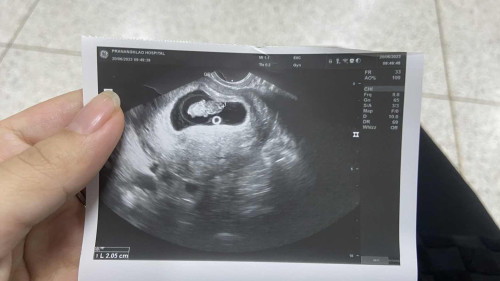

แบ่งปันภาพอัลตราซาวด์9w กันค่ะ

ตั้งครรภ์ 9w+3d อัลตราซาวด์ผ่านทางช่องคลอดเมื่อวานน้องขนาดเล็กไปไหมคะ ขอดูภาพอัลตราซาวด์ของแม่ๆตอน 9w กันหน่อยค่ะ ไปรพ.รัฐคุณหมอบอกแค่ว่าน้องปกติมีหัวใจเต้น #ขอบคุณล่วงหน้านะคะ #ท้องแรก

9วีค ค่ะ คุณหมอบอกปกติค่ะ หัวใจเต้นปกติขนาด 1.8 เองค่ะ